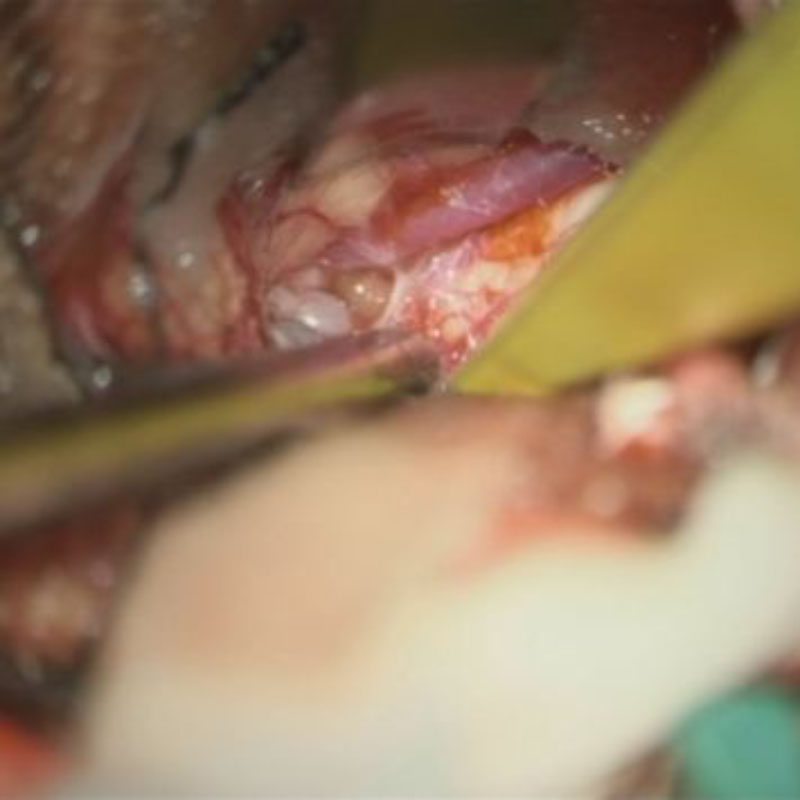

No.No.62 摘出前

No.No.62 摘出中1

No.No.62 摘出中2

No.No.62 摘出後

CT/MRにより完全に摘出されたことが確認された